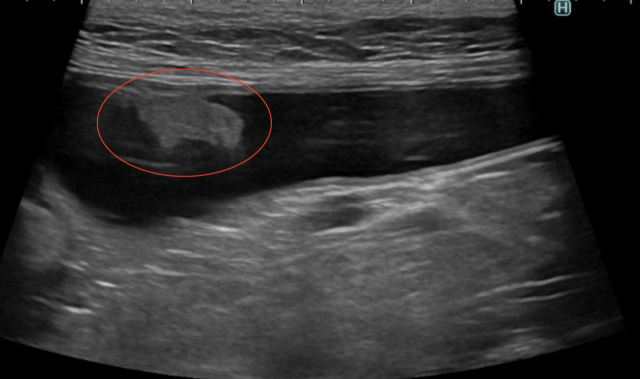

レントゲン検査とエコー検査を実施したところ、膀胱にしこりが認められ(下のエコー画像の赤丸)、検査の結果、移行上皮癌と診断されました。